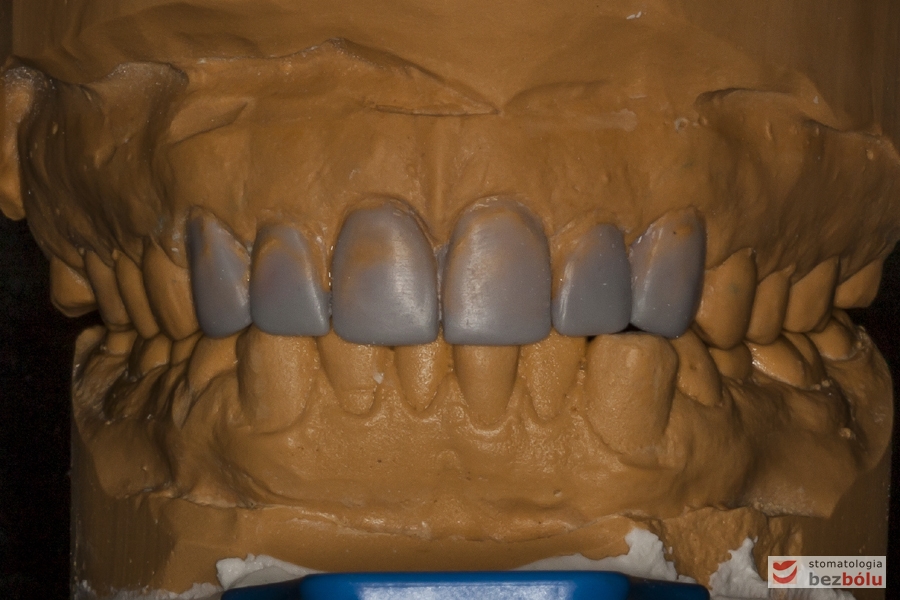

Modele gipsowe w artykulatorze - nawoskowane zęby od kła do kła w celu ich wydłużenia

Modele gipsowe w artykulatorze – nawoskowane zęby od kła do kła w celu ich wydłużenia